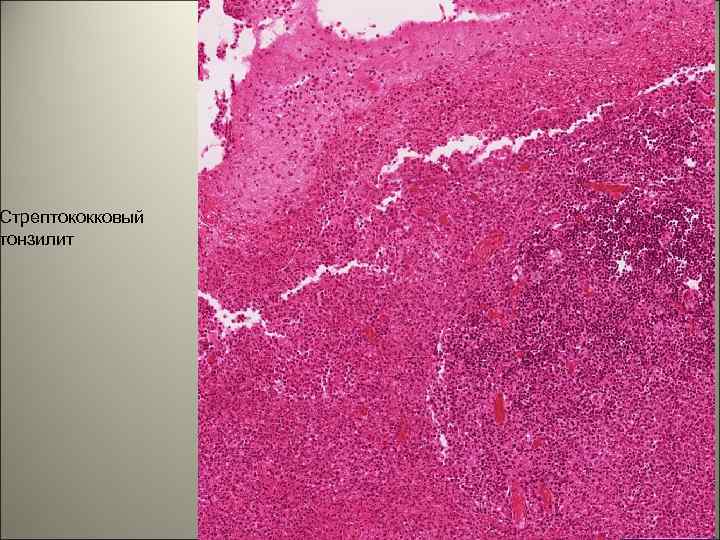

• Заболевание начинается остро. • Нарастают симптомы интоксикации: часто появляются рвота, головная боль, слабость. • При объективном обследовании выявляют яркую гиперемию зева, увеличение миндалин, а также регионарных лимфатических узлов, тахикардия. 138

• Миндалины увеличены, иногда на них отмечаются некротические изменения, покрытые фибринозными пленками. Регионарные узлы увеличены, болезненны. Возможно увеличение печени и селезенки. 139

Стрептококковый тонзилит 140